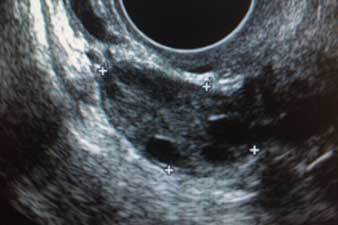

Realizaremos una ecografía transvaginal con el objetivo de valorar la morfología del útero y ovarios. Con una sencilla ecografía podemos detectar tanto malformaciones uterinas,presencia de miomas o pólipos endometriales y descartar la presencia de tumoraciones ováricas.

Ecografía de ovario normal